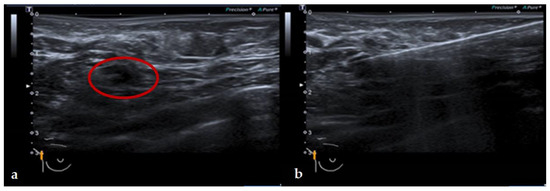

2.3. Magnetic Guided Axillary UltraSound (MagUS) and Core Needle Biopsy (CNB)